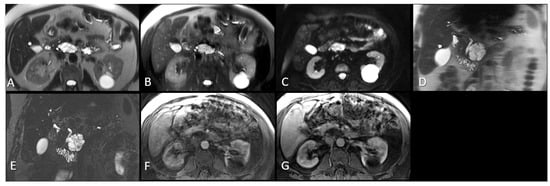

All MR examinations were performed on 1.5 T MRI scanners: n = 36 (Siemens Medical Solutions, Erlangen, Germany); n = 7 (Philips Medical Systems, Amsterdam, The Netherlands); n = 5 (General Electric Medical Systems, Waukesha, WI, USA); n = 2 (Hitachi Medical Corporation, Tokyo, Japan); n = 1 (Toshiba-MEC, Tokyo, Japan); n = 1 (Marconi Medical Systems, Cleveland, OH, USA) using standard pulse sequences. T2 weighted axial images: echo time (TE) = 60–184 ms, repetition time (TR) = 437–22,000 ms, flip angle (FA) = 90–180 ms, slice thickness =3.8–10 mm, field of view (FOV) = [310–480] × [233–400] mm2, matrix = [192–256] × 512, number of excitations/averages (NEX) = 1–4, in-plane pixel resolution 0.61–1.76 mm. T2 weighted fat saturated axial images TE = 61–125 ms, TR = 710–15,000 ms, flip angle = 68–180 ms, slice thickness = 3.8–10 mm, FOV = [194–310] × [450–480] mm2, matrix = [192–256] × 512, NEX (averages) = 1–3, in-plane pixel resolution 0.61–1.76 mm. T2 weighted coronal images: TE = 67–447 ms, TR = 399–1915 ms, flip angle = 90–180 ms, slice thickness = 4–10 mm, FOV = [298–300] × 480 mm2, matrix = [224–240] × 512, NEX (averages) = 1–2, in-plane pixel resolution 0.59–1.56 mm. MRCP coronal images: TE = 120–675 ms, TR = 1000–8062 ms, flip angle = 90–180 ms, slice thickness = 1–3 mm, FOV = 194 × [430–450] mm2, matrix = 192 × [768–986], NEX (averages) = 1–2, in-plane pixel resolution 0.38–1.77 mm. T1 weighted fat saturated axial arterial phase: TE = 1–16 ms, TR = 3–475 ms, flip angle = 10–90 ms, slice thickness = 2.5–10 mm, FOV = [200–280] × [410–480] mm2, matrix = [160–240] × 512, NEX (averages) = 1, in-plane pixel resolution 0.55–1.60 mm. DWI axial images b = 50:TE = 69–71 ms, TR = 3550 ms, flip angle = 90 ms, slice thickness = 8 mm, FOV = 380 × 450 mm2, matrix = 256 × 256, NEX (averages) = 1, in-plane pixel resolution 1.48–1.76 mm. The MRI sequences included in this study are shown in Figure 1.

Figure 1.

MRI sequences evaluated in this study. (A). Axial T2W HASTE. (B). Axial T2W fat saturated. (C). Axial DWI (low b = 50). (D). Coronal T2W HASTE. (E). Coronal MRCP. (F). Axial T1W fat saturated post contrast arterial phase, (G). Axial T1W fat saturated post contrast venous phase. The maximum diameter was measured on the coronal MRCP series for this uncinate process pathology proven pancreatic IPMN. MRI: Magnetic resonance imaging. W: Weighted. HASTE: Half-Fourier single-shot turbo spin-echo. DWI: Diffusion weighted imaging. IPMN: Intraductal papillary mucinous neoplasm. MRCP: Magnetic resonance cholangiopancreatography.